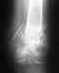

Здравствуйте !У меня варусная деформация локтевого сустава,хотел бы узнать можно ли сделать операцию или нет ? если у кого нибудь были похожие травмы или можете посоветовать что нибудь.Ответьте пожалуйста .. Заранее спасибо !!!

и у моего сына тоже..после перелома-ВАРУСНАЯ деформация локт сустава.ВОЗНИКЛА кантрактура ..ЧТО ДЕЛАТЬ? можно ли прооперировать снова и есть ли гарантия...что сростется правильно?!